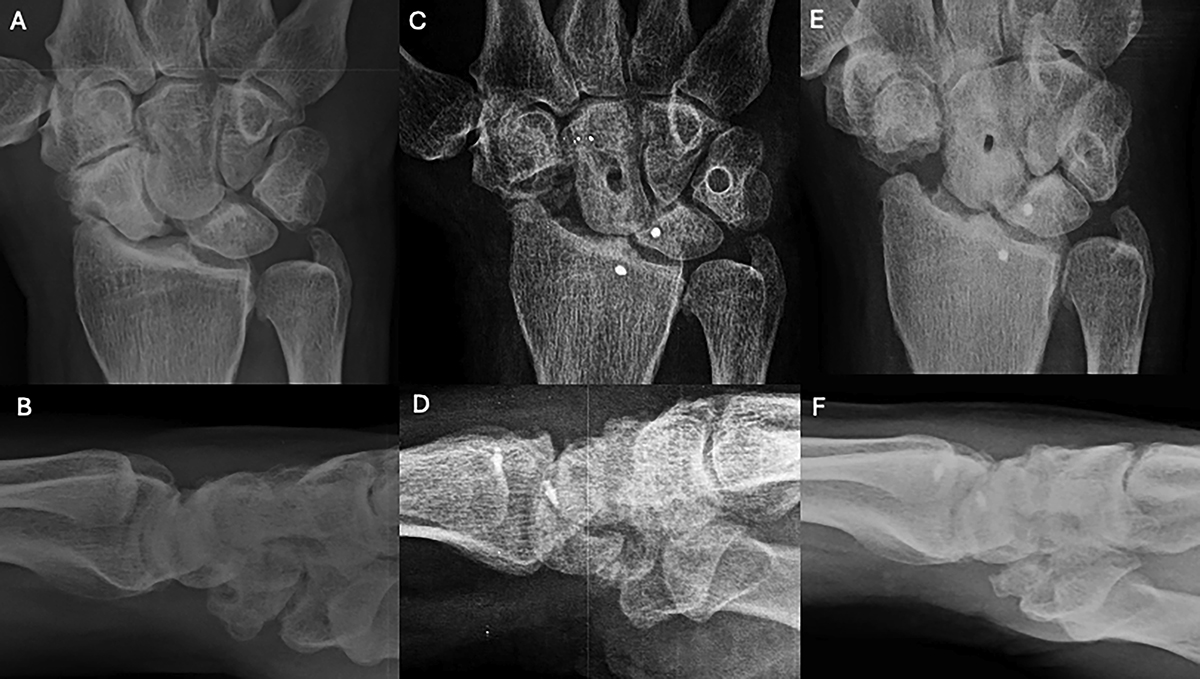

Clinical case of ECRB Transosseous C-T and Scaphoid excision. A and B. Preoperative wrist X-rays of SLAC stage II (AP and Lateral views). C and D. Postoperative wrist X-rays (AP and Lateral views) after 2 months. E and F. Postoperative wrist X-rays (AP and Lateral views) after 2 years. Source: Dr. Emmanouil Apergis.